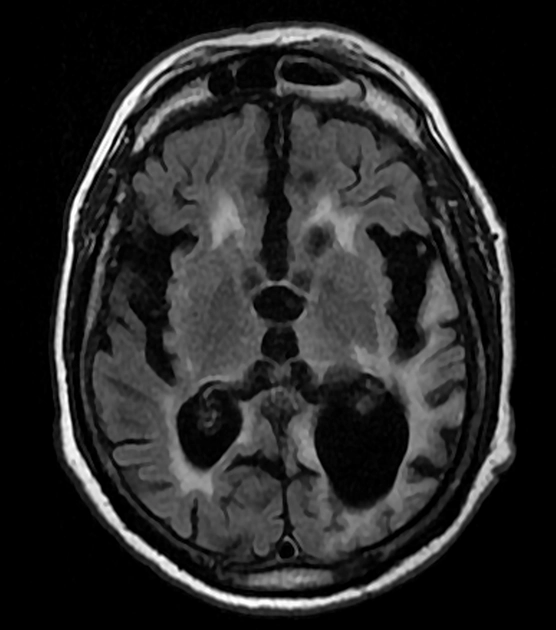

• Nhiễm sắt bề mặt kinh điển (Superficial Siderosis, Classical- SS)